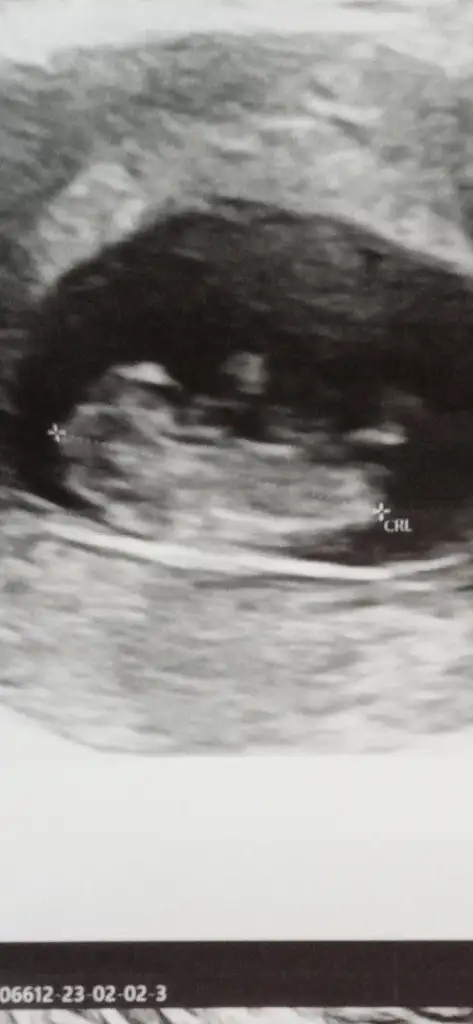

Rica etsem banada bakarmisiniz çok merak ediyorum 🥰☺️❤️

Eklentiler

• Screenshot_20230204-002246.webp

Screenshot_20230204-002246.webp

13,7 KB · Görüntüleme: 92

• IMG_20230202_182730_387.webp

IMG_20230202_182730_387.webp

23,3 KB · Görüntüleme: 67

• IMG_20230202_182706_519.webp

IMG_20230202_182706_519.webp

25 KB · Görüntüleme: 77

• IMG_20230202_182701_639.webp

IMG_20230202_182701_639.webp

27 KB · Görüntüleme: 83